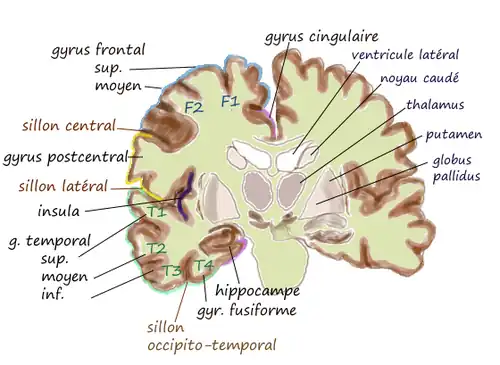

Le gyrus cingulaire est un gyrus du lobe limbique du cortex cérébral. Il est situé sur la face médiale des hémisphères, au-dessus du corps calleux. Au-dessus, il est séparé du gyrus frontal supérieur par le sillon cingulaire et du précuneus par le sillon sous-pariétal. En dessous, sa limite est le sillon du corps calleux. Au niveau du splénium du corps calleux, le gyrus cingulaire se rétrécit dans l'isthme qui se poursuit par le gyrus parahippocampique[1].

| Gyrus de la face médiale | Coupe coronale |